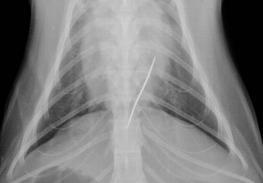

26.10.11 Evelin war aufgefallen, daß sich LaLuna sehr merkwürdig verhielt. Sie schien stumm vor sich hin zu leiden, ließ sich nicht anfassen und bewegte sich kaum noch. Evelin vermisste aus ihrer Näharbeit einen Faden, an dem noch eine 5cm lange Nadel hing. Mit den schlimmsten Befürchtungen brachten wir sie sofort zum Tierarzt nach Lefkas, wofür uns Eddy sein Auto lieh. Mehrere Röntgenbilder brachten Gewißheit - die Nadel steckte in der Speiseröhre.

Alle Versuche sie irgendwie zu entfernen schlugen fehl. Wir entschieden uns nach Empfehlung des Arztes für eine sofortige Notoperation. LaLuna wurde daraufhin für den Eingriff vorbereitet und nachdem der Kollege eintraf wurde operiert. Wir konnten nicht bleiben, denn es wusste keiner der Ärzte, wie lange es dauern könnte. Spät am Abend rief uns Nikos, der behandelnde Tierarzt an und sagte, daß die OP gut verlaufen ist, aber man noch nichts über den Erfolg sagen kann. Am nächsten Tag besuchte ich sie, aber sie war noch zugedröhnt von der Narkose und den Schmerzmitteln. Nikos sagte, daß sie den Bauch und den Magen geöffnet hatten und nach langer Suche endlich den Faden fanden und zu fassen bekamen. Damit haben sie dann vorsichtig die Nadel heraus ziehen können. Es wäre nur eine kleine Verletzung der Speiseröhre enstanden. Diese ist aber trotzdem mit am kritischsten, da nichts durch die Verletzung in den Brustraum gelangen darf. Glücklicherweise würden aber solche Verletzungen binnen weniger Tage verheilen.